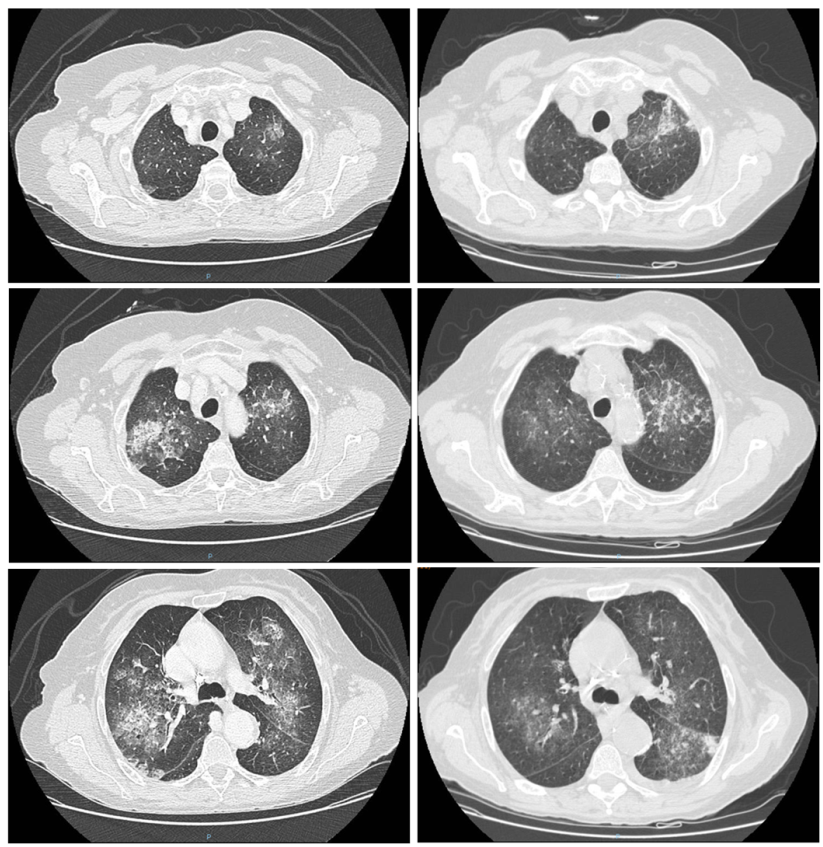

Angesichts dieser Daten und der Tatsache, dass die Patientin kürzlich eine weitere Lungenentzündung erlitten hatte, wurde eine weitere CT-Untersuchung des Brustkorbs durchgeführt. Wie aus den Bildern ersichtlich, bestätigte die CT-Untersuchung das Vorhandensein mehrerer milchglasartiger Trübungen in der Lunge, wobei sich einige Läsionen im Vergleich zur vorherigen CT-Untersuchung verbessert und andere verschlechtert hatten.

Hochauflösende CT-Aufnahme des Brustkorbs. Die Bilder auf der linken Seite beziehen sich auf die CT-Aufnahme, die einen Monat zuvor durchgeführt wurde; die Bilder auf der rechten Seite beziehen sich auf die CT-Aufnahme, die während des aktuellen Krankenhausaufenthalts durchgeführt wurde. Der Vergleich zeigt erhebliche Veränderungen der zuvor beschriebenen Trübungen, von denen sich einige verbessert haben (rechte Lunge) und andere radiologisch verschlechtert haben (Spitze und oberes Segment der linken Lunge).